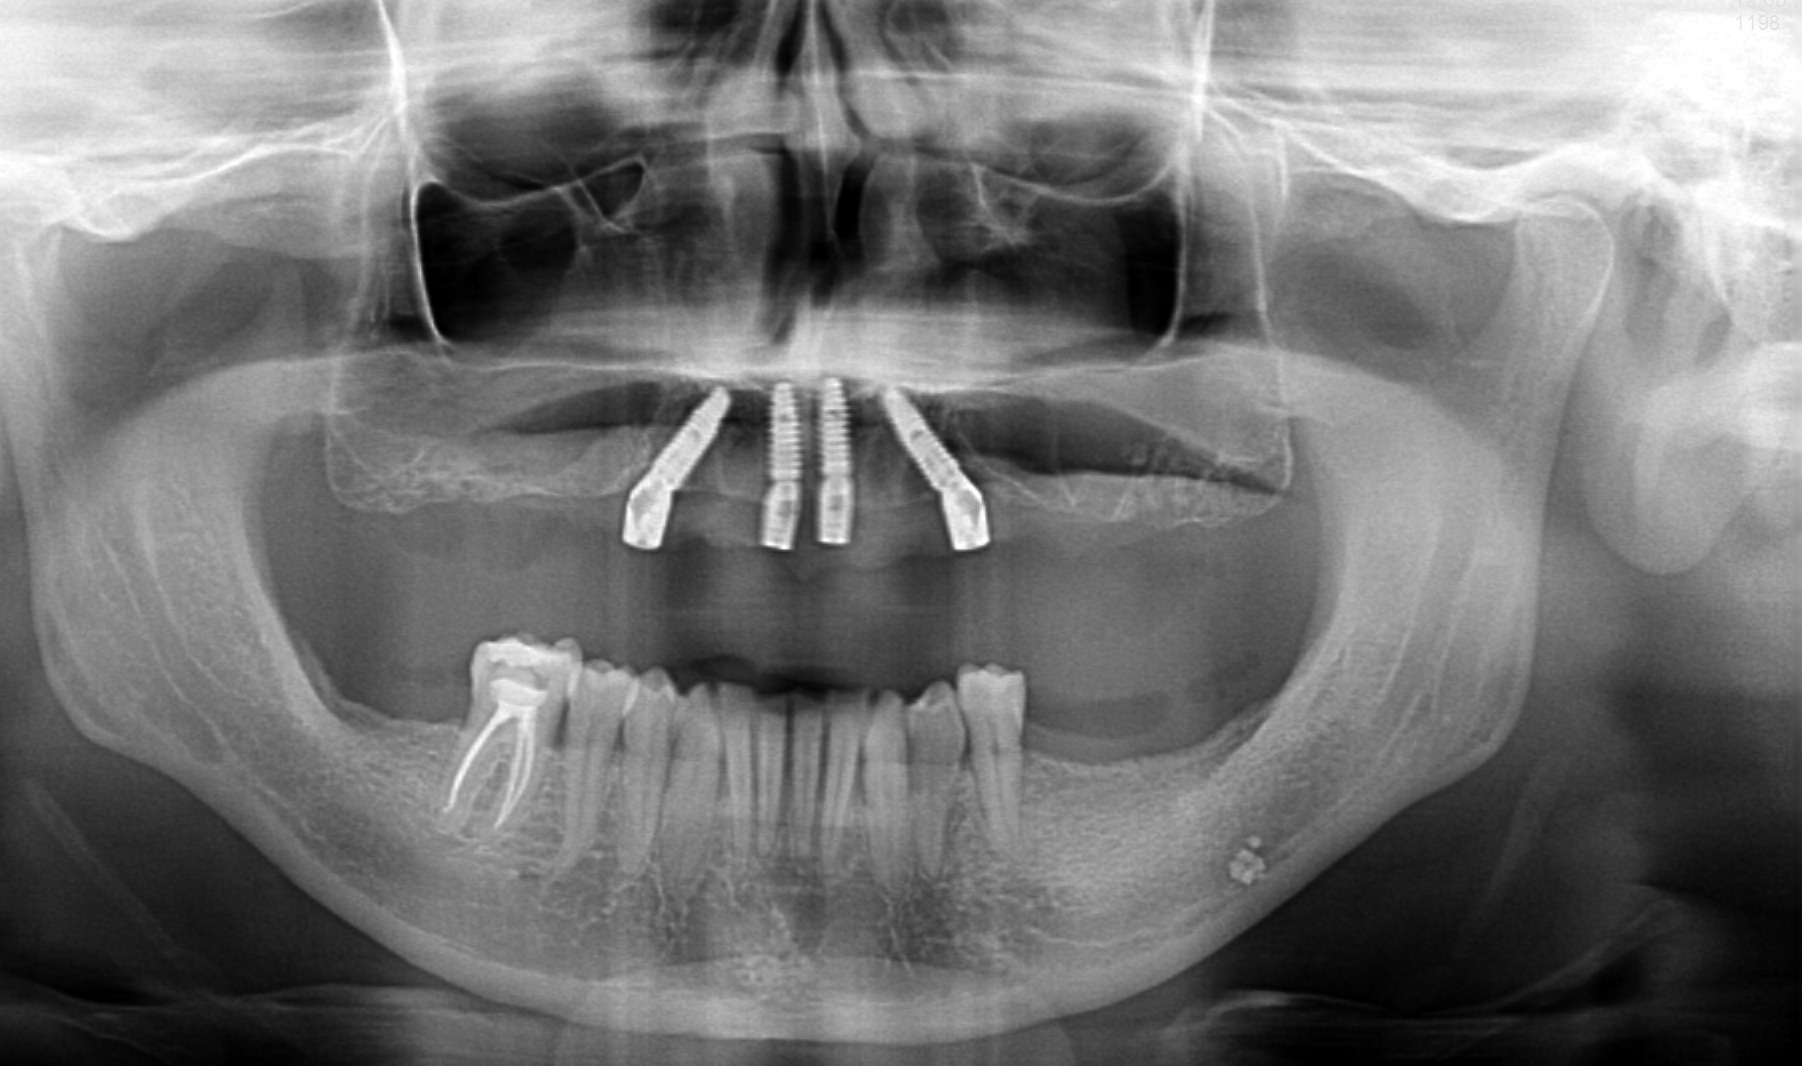

Metoda All On X to rewolucyjne podejście do odbudowy całej szczęki na implantach. Polega na osadzeniu pełnej protezy stałej na odpowiedniej liczbie implantów (zwykle 4-6), strategicznie rozmieszczonych w kości szczęki lub żuchwy. Liczba implantów jest dobierana indywidualnie do każdego pacjenta – stąd nazwa “All On X”, gdzie X oznacza optymalną dla danego przypadku liczbę wszczepów.

Kluczowe cechy metody:

– Kompleksowe rozwiązanie dla całej szczęki w jednej wizycie chirurgicznej

– Pełna odbudowa uzębienia na 4-6 implantach

– Możliwość natychmiastowego obciążenia protezą tymczasową

– Trwałe, stabilne rozwiązanie bez konieczności wyjmowania protezy